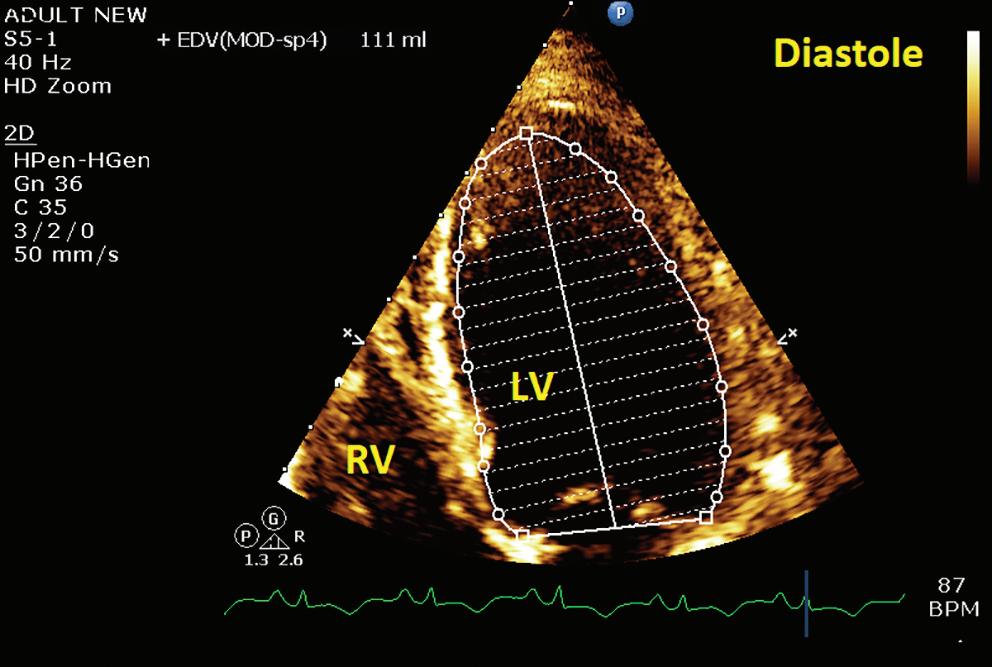

JAPSC 2022 - Volume 1 by Radcliffe Cardiology - Issuu